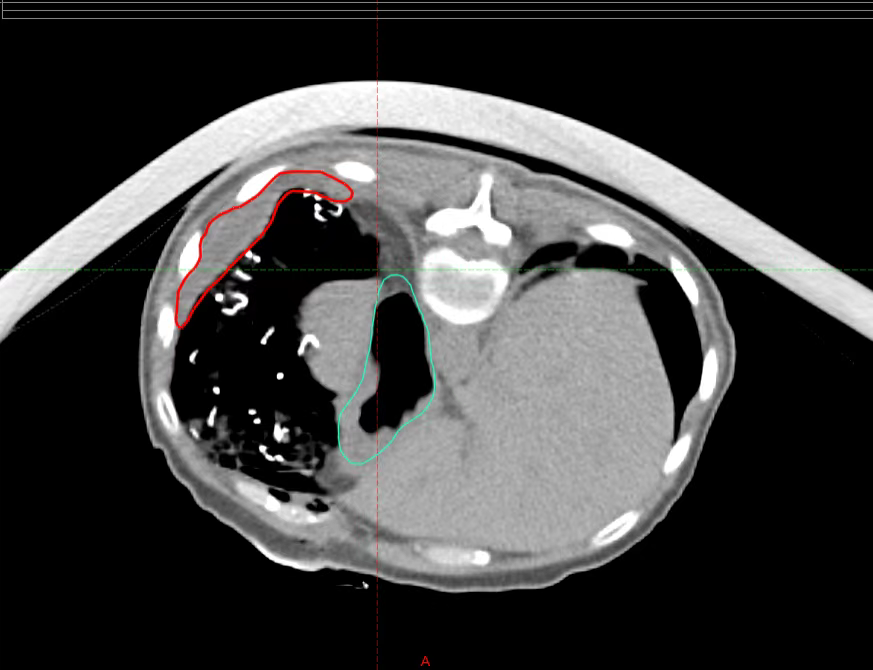

The relationship between the lesion and the stomach after placing the gauze pad (red indicates the lesion, blue indicates the stomach)